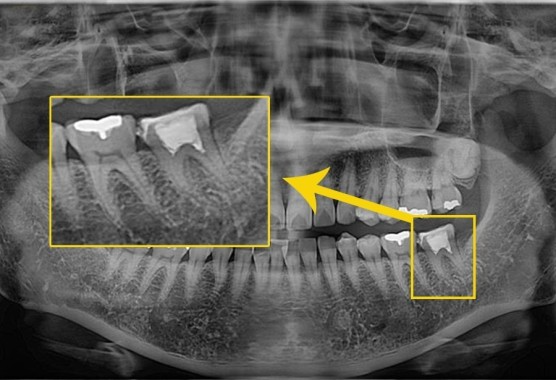

[2022. 06. 22 초진 시 환자분 구강 상태]

22년 6월 내원하신 환자분으로 # 37  치아에 금이 가서 타원에서 부분신경치료 후

금관수복을 하였으나 저작시 통증이 계속되서 발치여부 진단을 위해 내원하셨습니다.

[2022. 06. 22 초진 시 구강 상태]